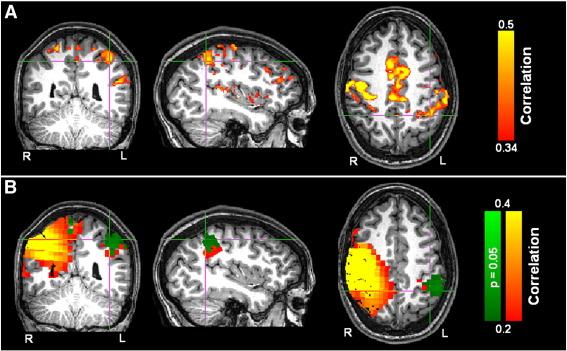

Functional connectivity (FC) between brain regions is thought to be central to the way in which the brain processes information. Abnormal connectivity is thought to be implicated in a number of diseases. The ability to study FC is therefore a key goal for neuroimaging. Functional connectivity (fc) MRI has become a popular tool to make connectivity measurements but the technique is limited by its indirect nature. A multimodal approach is therefore an attractive means to investigate the electrodynamic mechanisms underlying hemodynamic connectivity. In this paper, we investigate resting state FC using fcMRI and magnetoencephalography (MEG). In fcMRI, we exploit the advantages afforded by ultra high magnetic field. In MEG we apply envelope correlation and coherence techniques to source space projected MEG signals. We show that beamforming provides an excellent means to measure FC in source space using MEG data. However, care must be taken when interpreting these measurements since cross talk between voxels in source space can potentially lead to spurious connectivity and this must be taken into account in all studies of this type. We show good spatial agreement between FC measured independently using MEG and fcMRI; FC between sensorimotor cortices was observed using both modalities, with the best spatial agreement when MEG data are filtered into the β band. This finding helps to reduce the potential confounds associated with each modality alone: while it helps reduce the uncertainties in spatial patterns generated by MEG (brought about by the ill posed inverse problem), addition of electrodynamic metric confirms the neural basis of fcMRI measurements. Finally, we show that multiple MEG based FC metrics allow the potential to move beyond what is possible using fcMRI, and investigate the nature of electrodynamic connectivity. Our results extend those from previous studies and add weight to the argument that neural oscillations are intimately related to functional connectivity and the BOLD response.

功能连接(FC)被认为是大脑处理信息的核心方式。异常的连接被认为与许多疾病有关。因此,研究 FC 的能力是神经影像学的一个关键目标。功能连接(fc)MRI 已成为一种流行的工具来进行连接测量,但该技术受到其间接性质的限制。因此,多模态方法是研究血流动力学连接背后的电磁动力学机制的一种有吸引力的手段。在本文中,我们使用 fcMRI 和脑磁图(MEG)研究静息状态 FC。在 fcMRI 中,我们利用超高磁场的优势。在 MEG 中,我们应用包络相关和相干技术来处理源空间投影的 MEG 信号。我们表明,波束形成提供了一种极好的方法,可以使用 MEG 数据在源空间中测量 FC。然而,在解释这些测量值时必须小心,因为源空间中的体素之间的串扰可能会导致虚假的连接,在这种类型的所有研究中都必须考虑到这一点。我们表明,使用 MEG 和 fcMRI 独立测量的 FC 之间具有良好的空间一致性;两种模态都观察到感觉运动皮质之间的 FC,当 MEG 数据被过滤到β频带时,空间一致性最佳。这一发现有助于减少每种模态单独存在的潜在混淆:虽然它有助于减少 MEG 产生的空间模式的不确定性(由不适定的逆问题引起),但添加电磁度量法确认了 fcMRI 测量的神经基础。最后,我们表明,多个基于 MEG 的 FC 指标有可能超越使用 fcMRI 可能实现的功能,并研究电磁连接的性质。我们的结果扩展了以前的研究结果,并为神经振荡与功能连接和 BOLD 反应密切相关的论点增加了份量。